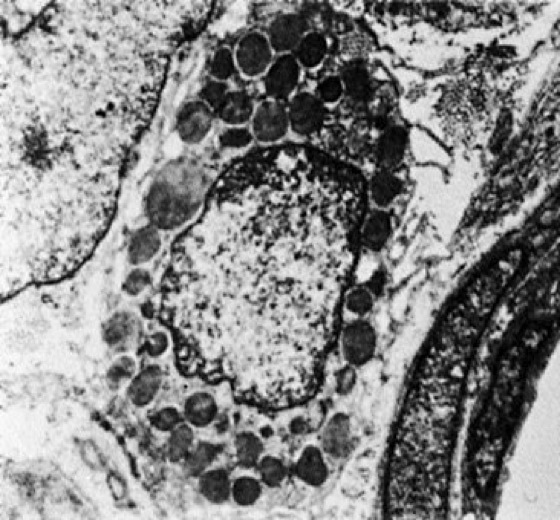

Mastzellen, Allergiezellen, E mast cells, Zellen des Immunsystems der Wirbeltiere und des Menschen, die zahlreich im Bindegewebe sowie im Gewebe des Nervensystems (Gewebs-Mastzellen;siehe Abb. ), seltener als Blut-Mastzellen im zirkulierenden Blut anzutreffen sind. Die Mastzellen-Granula enthalten die Mediatoren Heparin, Histamin, Bradykinin, bei manchen Tieren Serotonin sowie Enzyme und chemotaktische Faktoren für eosinophile und neutrophile Granulocyten. Durch Kontakt mit Antigen-Antikörper-Komplexen werden die Mastzellen zur Exocytose ihrer Granula angeregt. Dabei bindet die Mastzelle IgE durch spezifische Fc-Rezeptoren an ihrer Oberfläche. Die Vernetzung des Fc-Rezeptors bewirkt weiterhin die Synthese und Freisetzung von Leukotrienen und Prostaglandinen. Der besonders von Histamin und Serotonin ausgehende Reiz verursacht die typischen allergischen Reaktionen. Mastzellen kommen innerhalb von Nerven vor und können von Nervenendigungen angesteuert werden. Daher werden Mastzellen auch in Verbindung mit neuroimmunen Komponenten allergischer Erkrankungen gebracht. Allergie, anaphylaktischer Schock, Neuroimmunologie.

Gewebs-Mastzelle (elektronenmikroskopische Aufnahme)